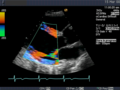

Die Aussagekraft der Sonografie kann erheblich durch die Anwendung des Doppler-Effekts erhöht werden. Man unterscheidet eindimensionale Verfahren (Pulsed-Wave-Doppler, Continuous-Wave-Doppler, auch als D-mode bezeichnet) von zweidimensionalen, farbkodierten Anwendungen (Farbdoppler – F-mode). Die Kombination B-Bild mit Pulsed-Wave-Doppler (PW-Doppler) nennt man auch Duplex.[4]

Doppler-Verfahren werden benutzt zur Bestimmung von Blutfluss-Geschwindigkeiten, zur Entdeckung und Beurteilung von Herz(klappen)fehlern, Verengungen (Stenosen), Verschlüssen oder Kurzschlussverbindungen (Shunts).

Bei der farbkodierten Doppler-Sonografie wird für einen großen Bereich eines konventionellen Ultraschallbildes (Color-Window) die örtliche Doppler-Frequenz (= mittlere Flussgeschwindigkeit) und deren Schwankungsbreite bestimmt. Damit möchte man die Turbulenz der Strömung abschätzen. Aufgrund der statistischen Bewegungen der Streuteilchen ist die Schwankungsbreite der Fließgeschwindigkeit jedoch stets größer als die Turbulenz. Das Ergebnis wird in Falschfarben auf dem B-Bild überlagert, also in Farbtönen von rot und blau für verschiedene Blutgeschwindigkeit und grün für Turbulenz. Hierbei steht üblicherweise die Farbe Rot für Bewegung auf den Schallkopf zu, während mit blauen Farbtönen Flüsse weg von der Sonde codiert werden. Bereiche der Geschwindigkeit 0 werden durch die Elektronik unterdrückt.

-

Anwendung des Doppler-Verfahrens bei einer Herzuntersuchung: Mitralklappeninsuffizienz -

Farb-Doppler und PW-Doppler. Innerhalb der Stenose ist wegen der hohen Flussgeschwindigkeit und des resultierenden Alias-Effekts die Geschwindigkeit in Blau kodiert. -